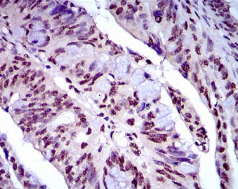

IHC    1/200 - 1/1000